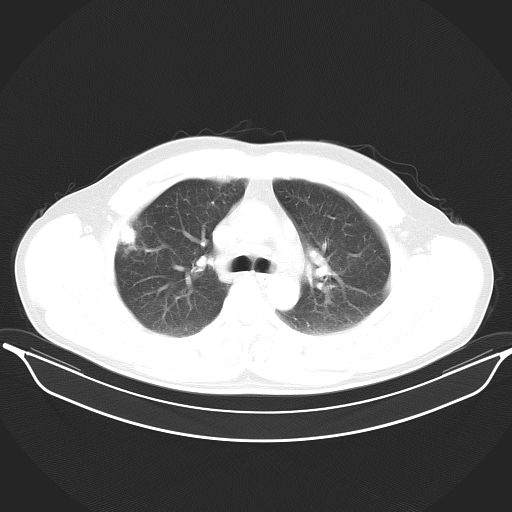

标题: CT25490:男,40岁,体检发现;无其它不适。 [打印本页]

标题: CT25490:男,40岁,体检发现;无其它不适。

考虑:1、过各敏性肺炎可能性大,建议定期复查。

多考虑结核。

考虑肺霉菌病。

转移性肺肿瘤不排除,建议结合相关检查考虑

考虑右下肺周围性肺癌并肺内多发转移,纵隔淋巴结转移!

考虑肺癌并肺内转移可能性大。

考虑过敏性肺炎,建议抗炎后复查,转移瘤及tb待排

支持 !考虑右下肺周围性肺癌并肺内多发转移,纵隔淋巴结转移,(气管前腔静脉后,隆突下,主动脉弓下都有了)

1、均为转移,原发灶不在肺内。2、肺癌肺转移。